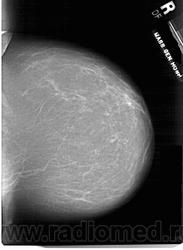

Со старением железистая ткань постепенно исчезает: прозрачность жировой ткани становится преобладающей с несколькими каркасами, связанными с опорными волокнистыми структурами.

Жирная (не плотная) грудь

Умеренно плотная грудь

Плотная грудь

Маммограммы представляют собой изображения структур, проецируемых на плоскость: плотная грудная маммограмма, следовательно, состоит из многих других структур, которые необходимо проанализировать, чем более жирная, пустая грудь. По этой причине диагностировать рак молочной железы труднее для моложе, чем для пожилых женщин.

Нажмите на миниатюрные картинки, чтобы получить увеличенный размер.